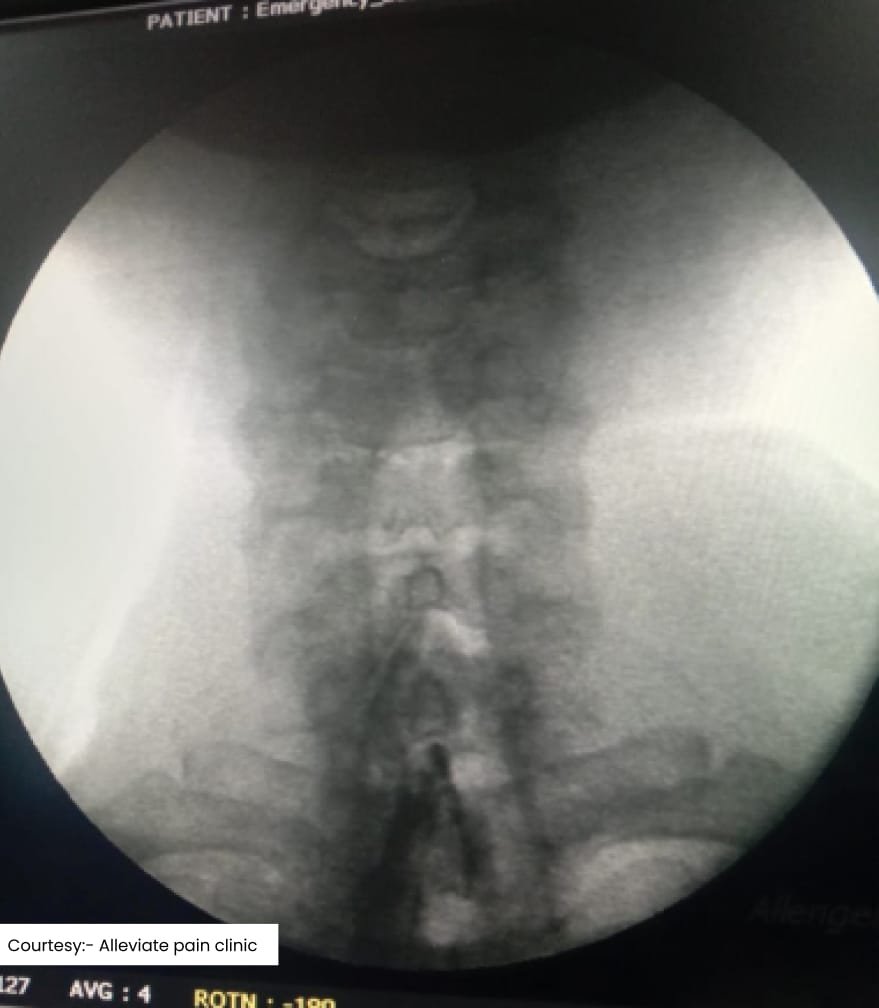

Scan Landscape

Stem cells injection of the facet joint done under fluoroscopy

Stem Cell Therapy

Stem cell therapy uses the body’s stem cells to regenerate damaged tissues. This cutting-edge treatment is ideal for conditions like degenerative disc disease and chronic joint pain. By promoting the regeneration of healthy tissues, stem cells can offer long-lasting relief from chronic low back pain.